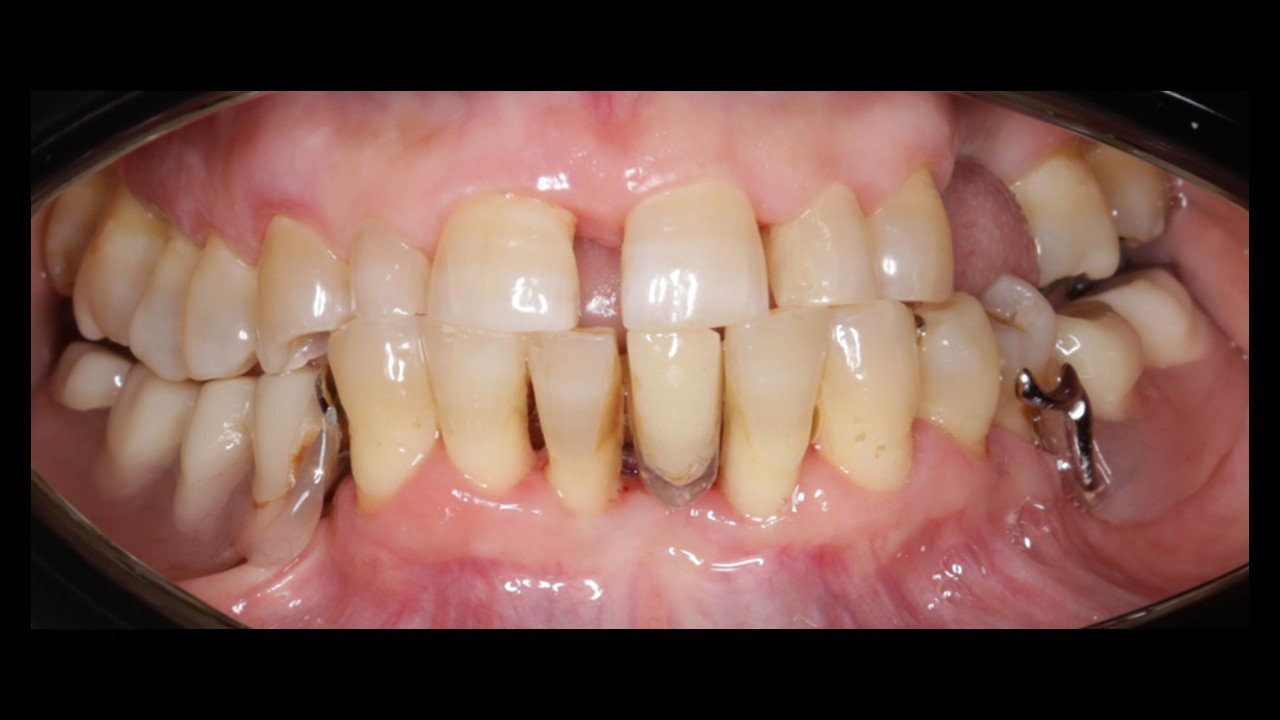

Datos personales paciente:

• Nombre: I.J.S.

• Edad: 56 años

• Género: FEM

Motivo de consulta: "Paciente deseaba asistir al dentista, sensación de dientes sueltos e interés en implantes

dentales"

• Hábitos: Hace 1 año que no fuma. Historial de periodos de tabaquismo, 1 a 3 cig al día, hace 5 años.